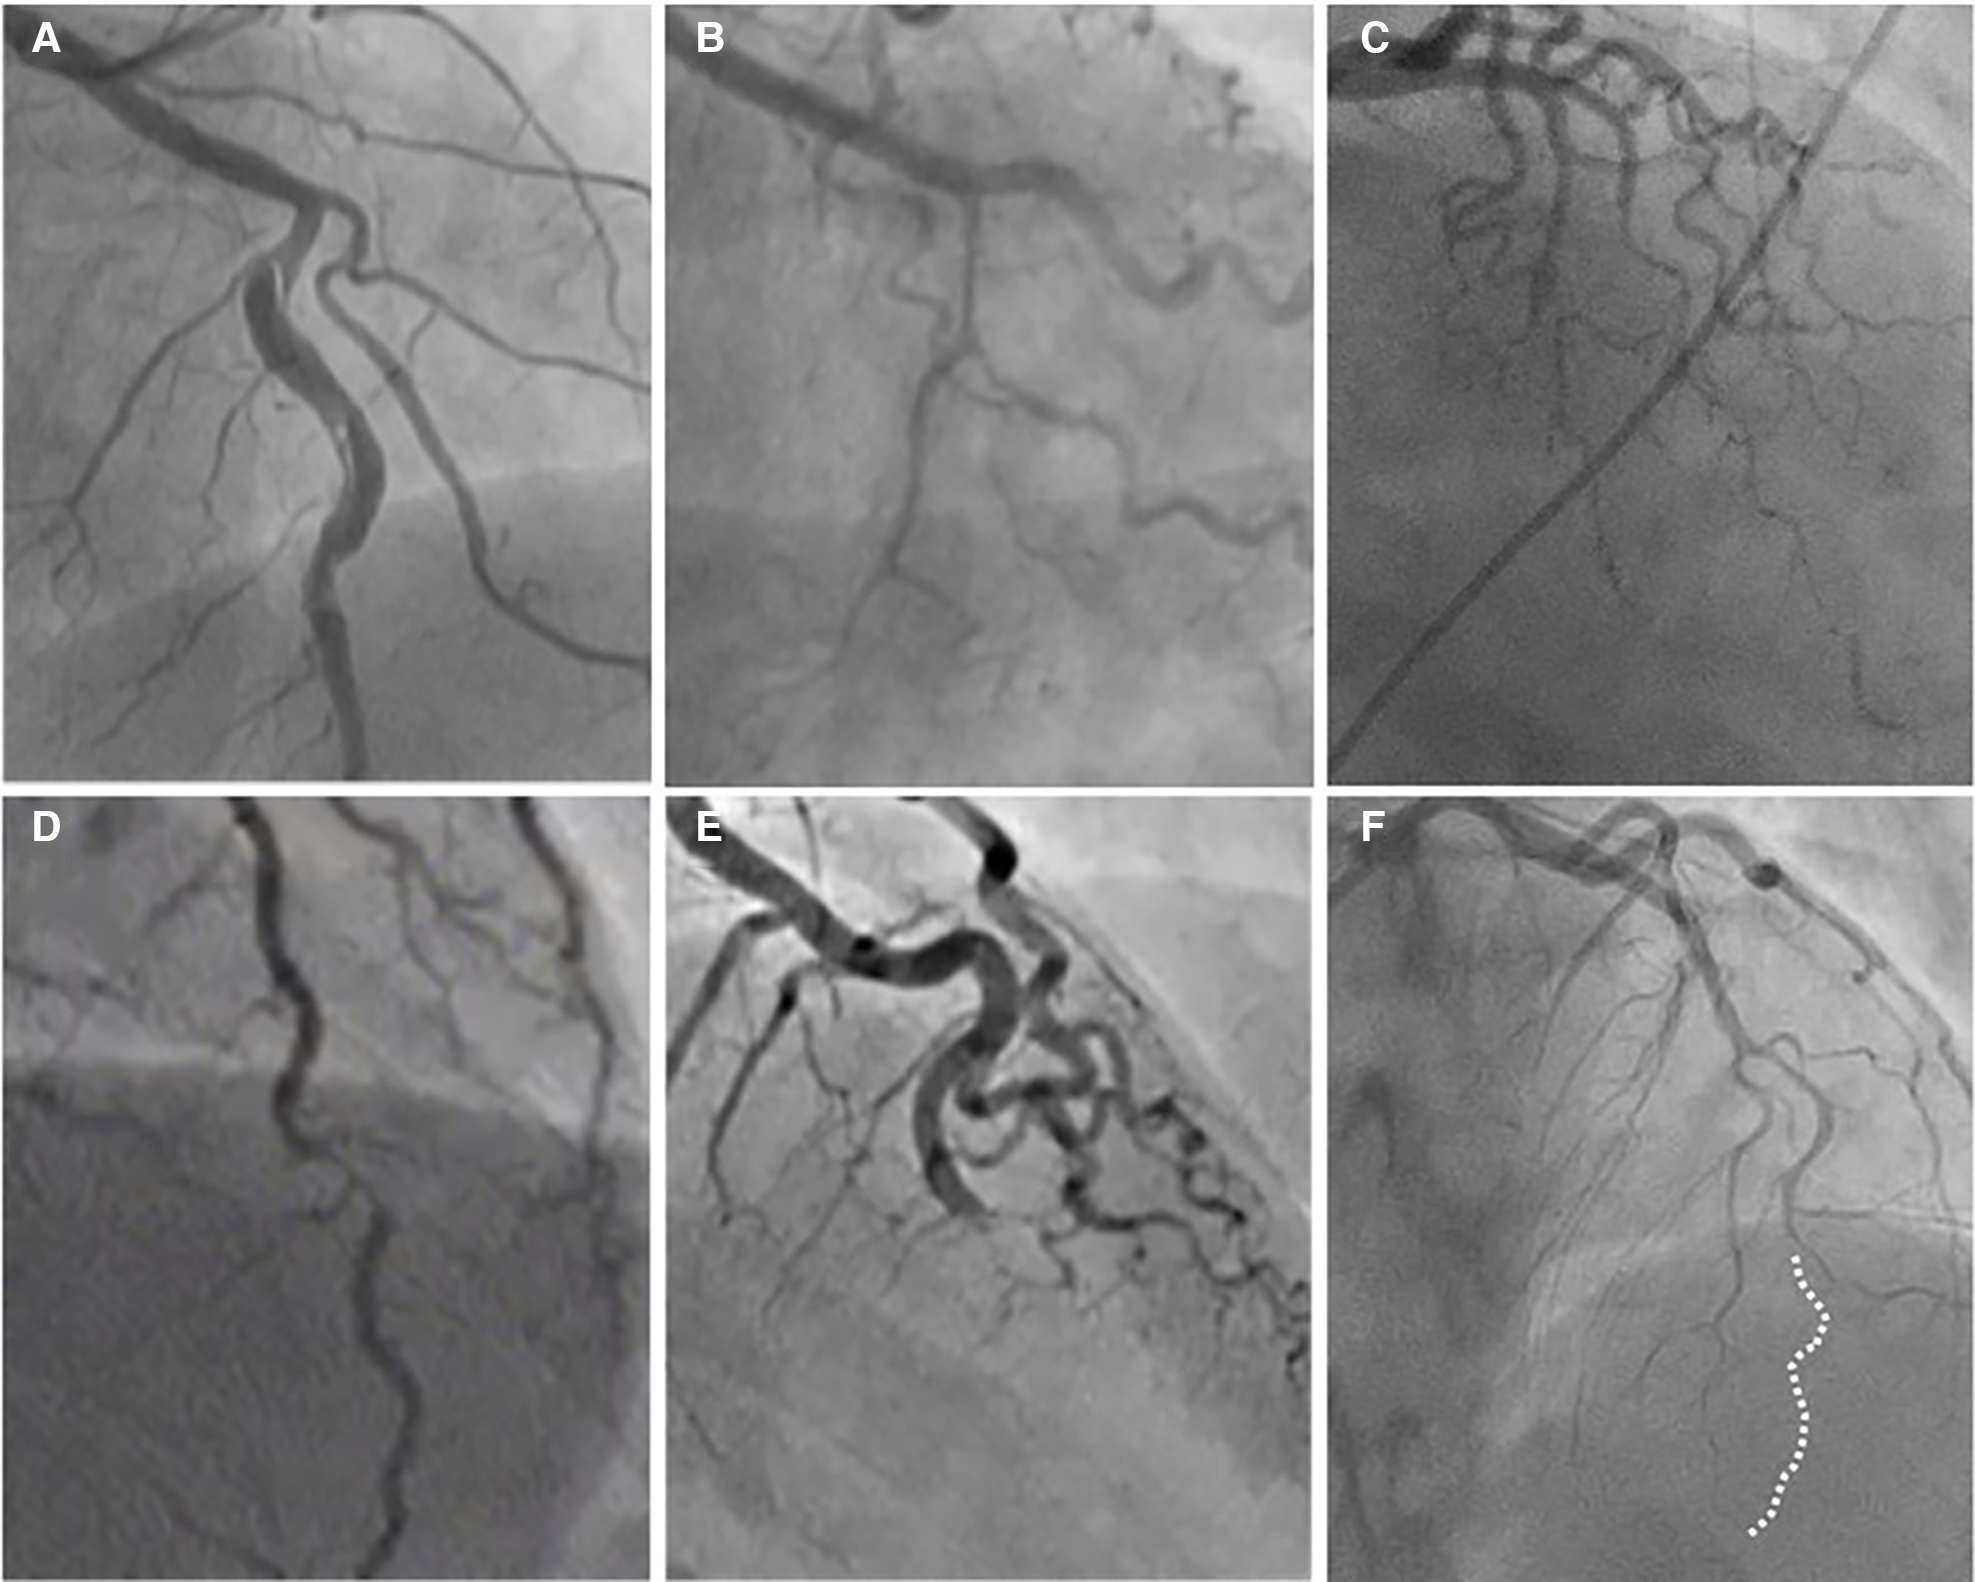

Type 1 accounts for about one-third of cases (16, 54), and represents the pathognomonic finding with multiple radiolucent lumen of linear filling defect (recognizable true and false lumen), usually with contrast dye staining in the false lumen. This appearance of SCAD is caused by the presence of an intimal tear which is identified in approximately 30% of SCAD cases (Figure 1, Figure 2A).

Figure 2

The angiographic appearance of SCAD. (A) Type 1-recognizable radiolucent flap; (B) type 2a-smooth diffuse stenosis with lumen restoration in the distal segment; (C) type 2b-smooth diffuse stenosis extending till the end of the artery; (D) type 3-resembling atherosclerosis; (E) type 4-distal occlusion; (F) an example of hybrid type SCAD- Type 2 in mid to distal segment with the transition to the Type 4-distal occlusion (dotted line depicts missing LAD).

Type 2 is the most common pattern (two-thirds of cases, Table 1) (16, 54), characterized by an abrupt change in the arterial calibre causing long and smooth stenosis caused by IMH, that tapers distally. It is located predominantly in the transition from mid to distal segments, most frequently affecting LAD. It is divided into Type 2a when there is restoration of the normal vessel in the distal segment (Figure 1, Figure 2B), and Type 2b, when the stenosis extends till the end of the artery (Figure 1, Figure 2C).

Type 3 is the least common (less than 5%) (16, 54), resembles atherosclerotic plaque with underlying focal, more localized IMH, thus difficult to diagnose without the assistance of intravascular imaging (Figure 1, Figure 2D).

Recently, additional Type 4 SCAD has been proposed to describe total occlusion, usually of a distal vessel, a pattern particularly challenging to diagnose (Figure 1, Figure 2E) (55).

However, all these types can coexist in the same vessel, generating hybrid types (Figure 2F).